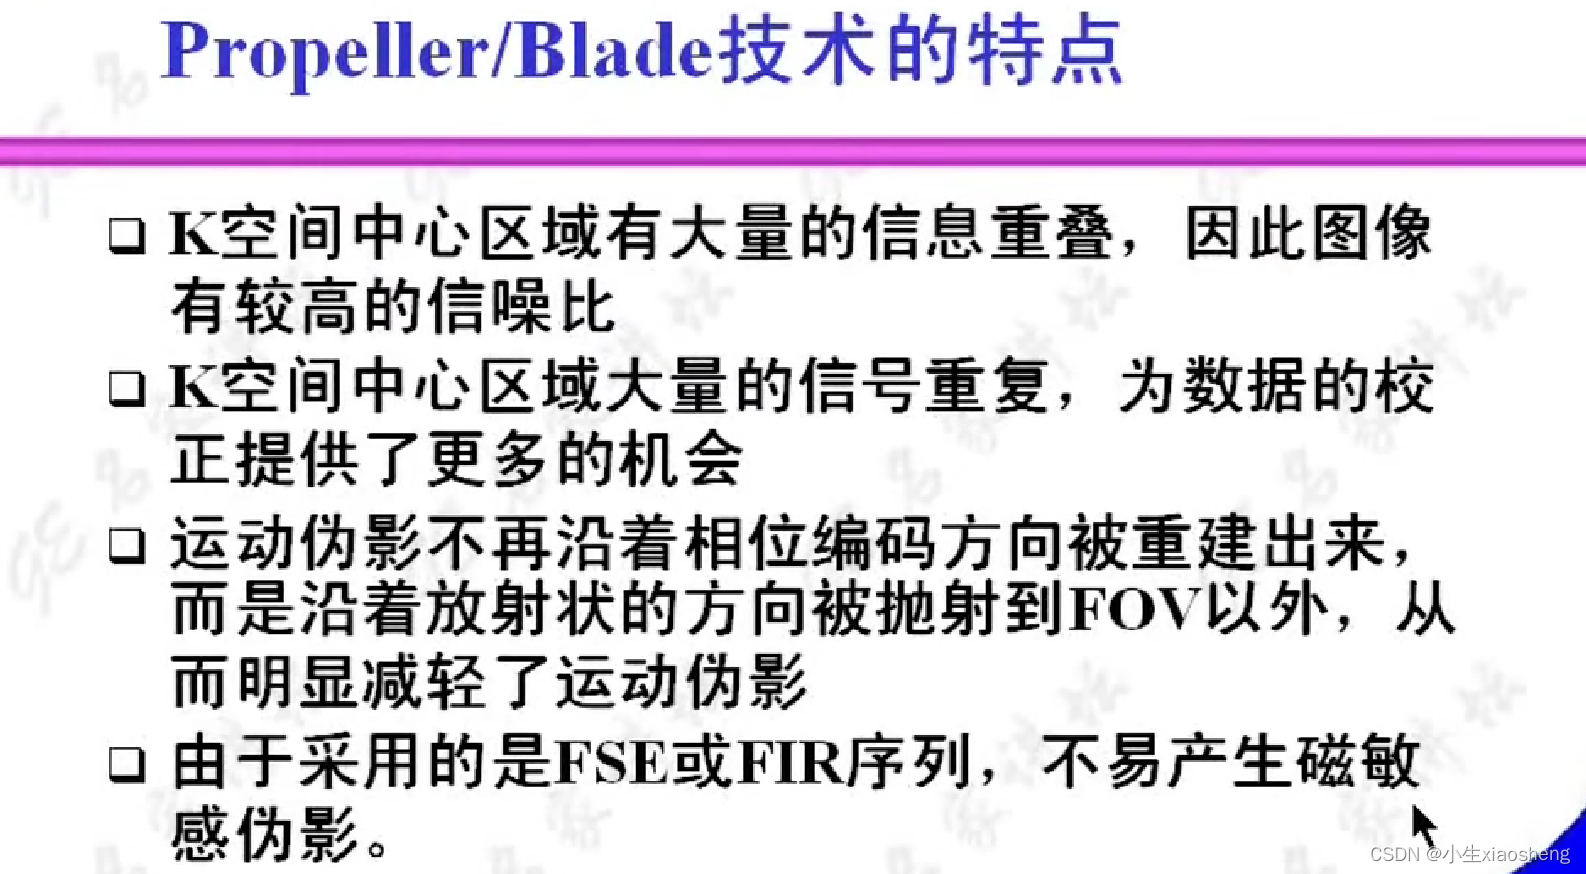

六、Propeller/Blade序列

螺旋桨和刀锋序列,其实也就是常规FSE(快速自旋)或IR-FSE(反转恢复)序列的K空间填充,可以和其他技术结合来减少运动伪影。

自旋回波--90度和180度填充K空间;反转恢复--在自旋的基础上两边加180度;梯度回波--消除每次脉冲留下的影响,以及波的次数;propeller==》K空间填充技术和FSE或FIR结合用于减少运行伪影;EPI==》采集方式,一次激发采集多个回波的形式但与单次不一样;PRESTO和GRASE==》前面几种的一种结合形成新的。